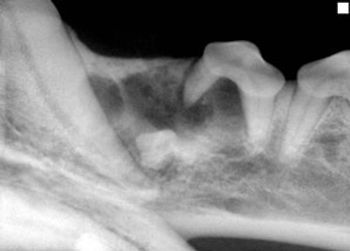

Tooth resorption is the most common dental problem in cats, with studies worldwide showing a prevalence rate (in cats presented for dental problems) of up to 75%.